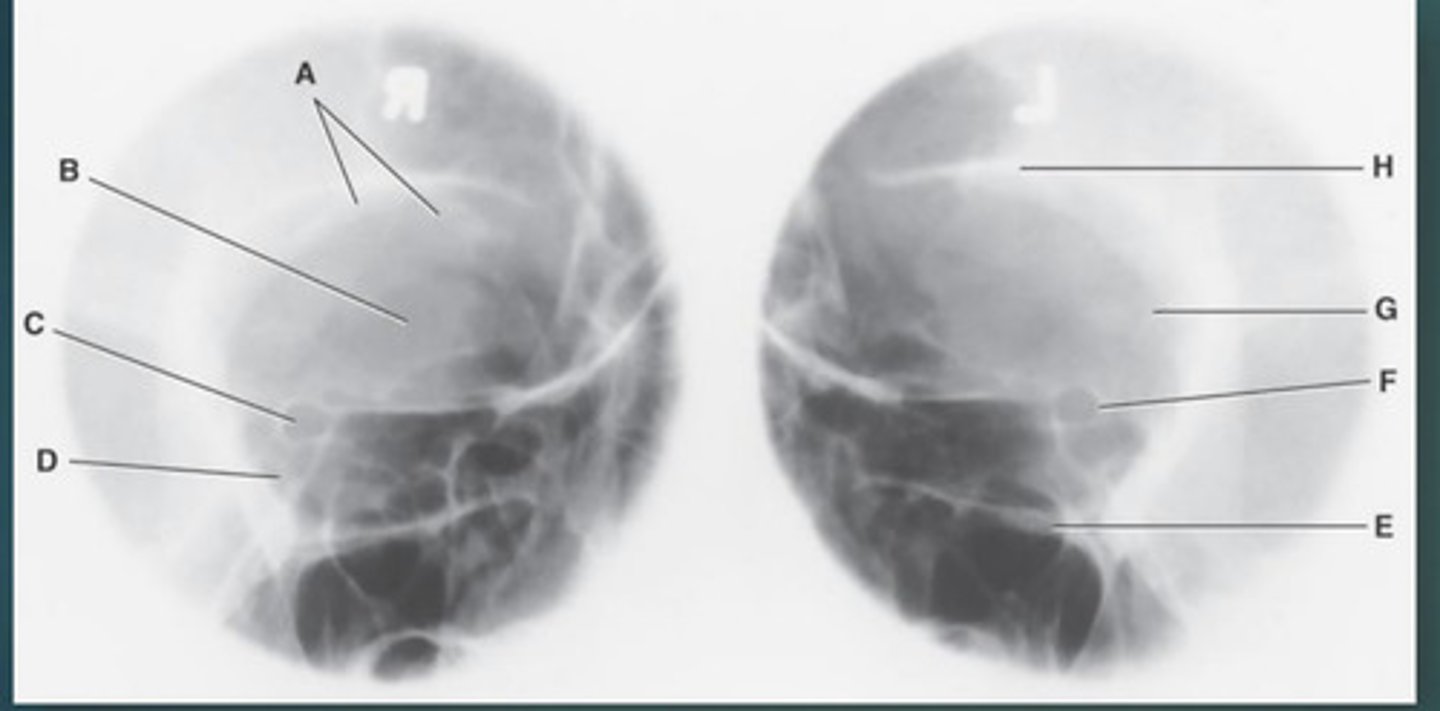

Lateral sinus

What position?

L. Orbital roofs

A.

L. Greater wings of sphenoid

B.

sella turcica of sphenoid

C.

L. Sphenoid sinus

D.

L. Rami of mandible

E.

L. Maxillary sinuses

F.

L. Ethmoid sinuses

G.

L. Frontal sinuses of frontal bone

H.